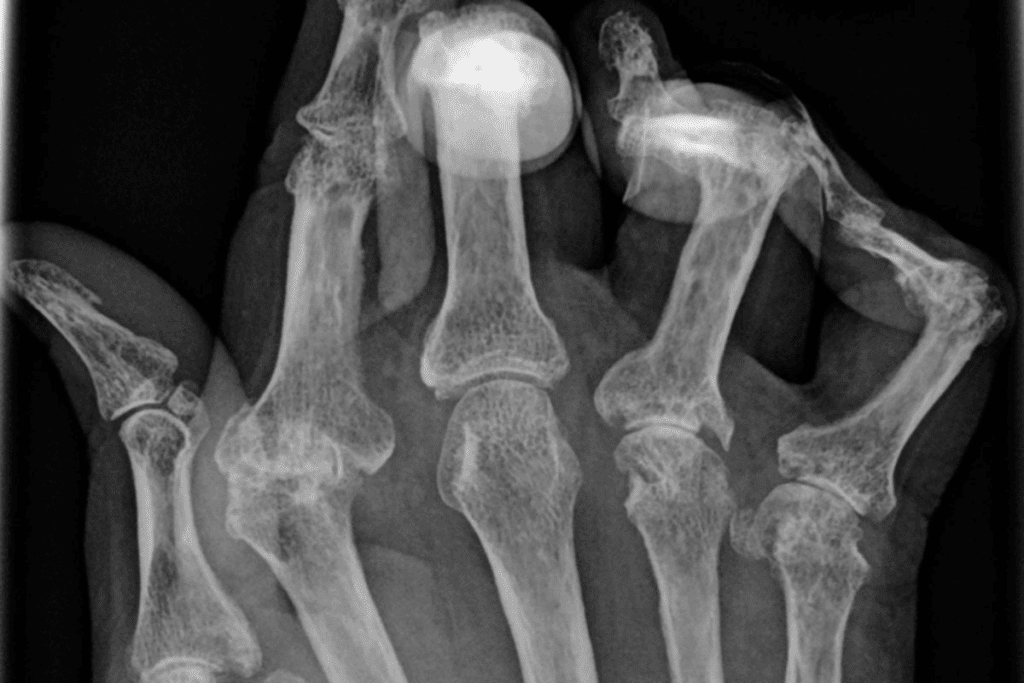

Conditions like arthritis can really hurt our joint mobility. Arthritis is a group of diseases that cause pain and swelling in the joints. We’ll look at how these conditions affect movement and what treatments are available.